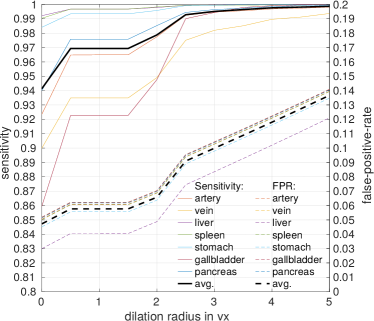

In the first stage, we apply simple thresholding in combination with morphological operations (hole filling and largest component selection) to get a mask of the patient’s body in a slice-by-slice fashion. This mask can be utilized as candidate region to reduce the number of voxels necessary to compute the network’s loss function and reduce the amount of input 3D regions shown to the CNN during training to about 40%. After training, the first-stage FCN is applied to each image to generate candidate regions for training the second-stage FCN (Fig. 3). We define the organ labels in the testing phase using the of the class probability maps. Any foreground label is then dilated in 3D using a voxel radius of . We compare the recall and false-positive rates of this first-stage FCN with respect to for both the training and validation sets in Fig. 2. gives good trade-off between high recall (99%) and low false-positive rates for each organ on our training and validation sets.